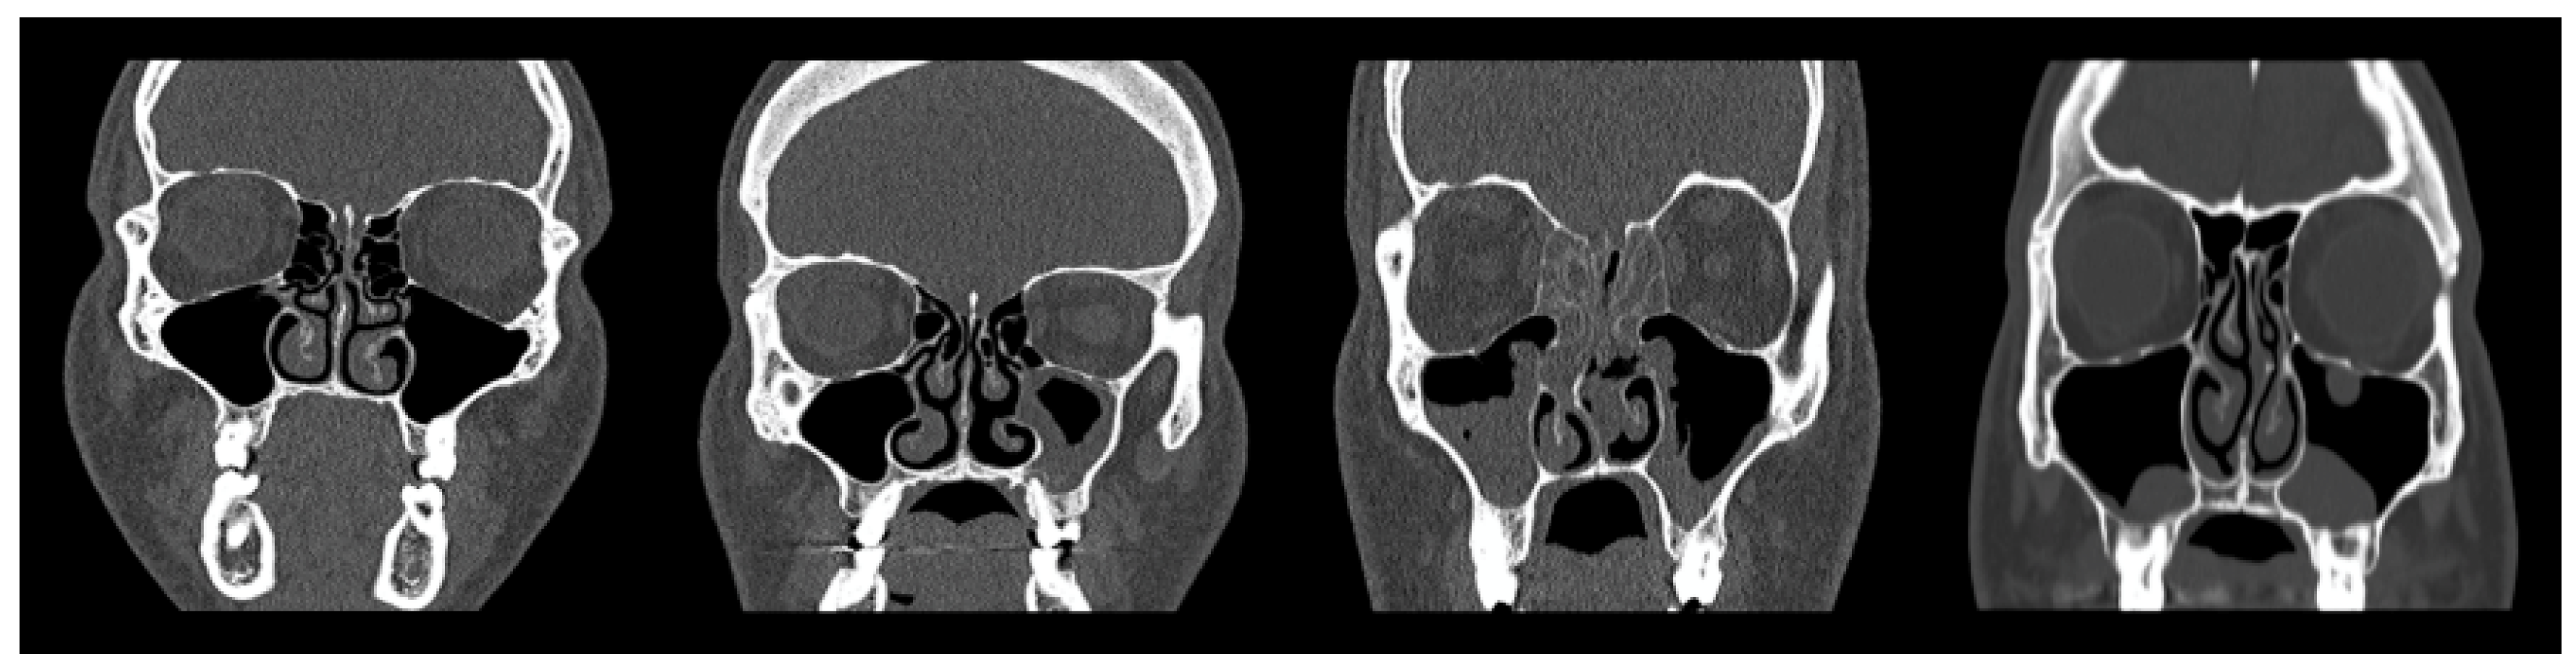

Following quality control, two experienced radiologists were engaged to manually evaluate and label the maxillary sinus findings into four distinct classes: Normal Maxillary Sinus (Normal MS), Opacified Maxillary Sinus (Opacified MS), Polyposis, and Retention Cysts. A visual illustration of the classification is presented in Figure 3, The first column (form left) column shows a normal sinus, the second column depicts partial opacification (Opacified MS), and the third and fourth columns represent Polyposis and Retention Cysts, respectively.

Figure 3. CT samples illustrating representative cases from each diagnostic category.